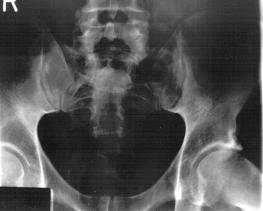

X-Rays and scans of the damaged right & left legs plus the pelvis

These x-rays were taken just after the accident. Some of the bones on the right leg have already been pushed back into the leg. The CT

scans show various views of the ankles and pelvis prior to any corrective surgery. Fibula bracing is clear in some of the images as well as

bracing that was used to secure the "open book" pelvis. In some of the last images it is apparent that the upper part of Liam’s left fibula is

broken. Liam was told that the pain he felt was most likely a muscle cramp. Nothing was done to repair this break and you will see in further

x-rays that the bone shifted and later fused in such a way as to add to the reduction of Liam’s leg length. The last photo shows the stint

used to block any potential blood clots from moving up.